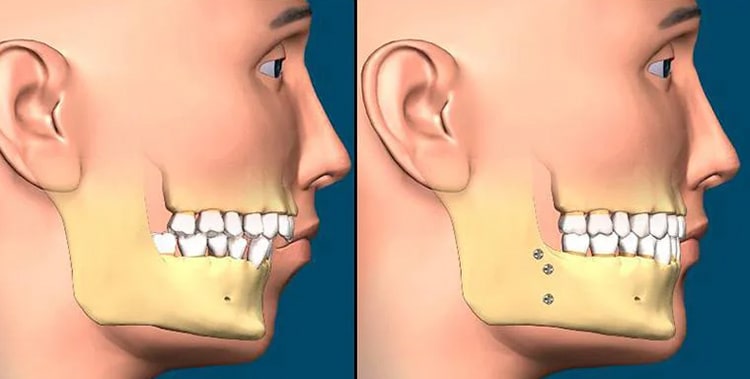

درمان ارتودنسی ممکن است برای اصلاح مشکلات فک پایین در شرایط خاص کافی باشد، در درجه اول زمانی که ناهماهنگی شدید نیست و شامل ناهماهنگیهای اسکلتی قابل توجهی نمیشود اما در ناهماهنگیهای قابل توجه اسکلتی زمانی که فک پایین به طور قابل توجهی در مقایسه با فک بالا بیرونزدگی یا عقبنشینی داشته باشد، باید هر دو فک تحت درمان قرار بگیرند.

**نکته: در مال اکلوژن های شدید مانند اپن بایت یا اوربایت شدید که ناشی از قرار گرفتن فک به جای تراز دندان است، معمولا به ترکیبی از ارتودنسی و جراحی برای اصلاح موثر نیاز است.

بیشتر بخوانید: رابطه ارتودنسی با جراحی فک (ارتوسرجری)